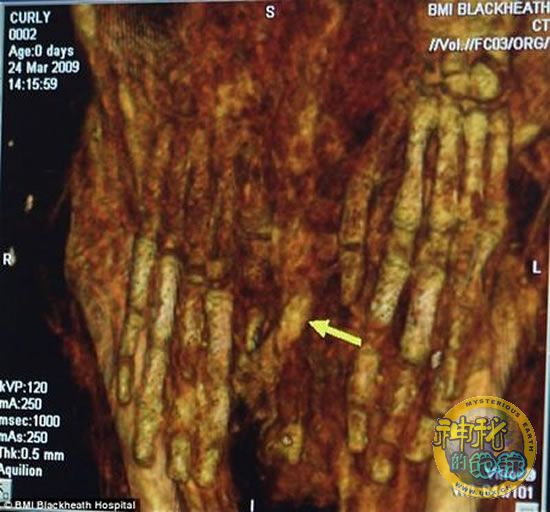

木乃伊扫描-箭头所指的是阳具

在一台CT扫描仪帮助下,科学家得以“刺破”紧紧包裹在3具小木乃伊外面,起到保护作用的一层层亚麻布条,进而揭示他们死后的细节。据悉,此项研究是在英国伦敦BMI布莱克海斯医院进行的。在扫描工作开始后仅一小时,科学家便得出了一项惊人发现。长期以来,人们一直认为其中一具头戴黄金面具的木乃伊是一个女孩,但扫描结果显示,这具木乃伊实际上是一个两岁左右的男孩。